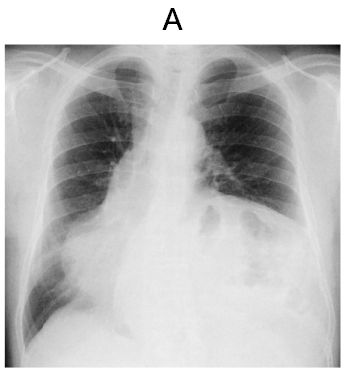

胸部エックス線写真の正面像(別冊No.5A)と側面像(別冊No.5B)を別に示す。

- 画像(別冊)では左横隔膜の挙上が予想される。

→ 高齢者に多い横隔膜弛緩症(diaphragmatic eventration)が最も一致。

- 胸部X線やCTで横隔膜の挙上と、時に腸管ガス像が見られる。